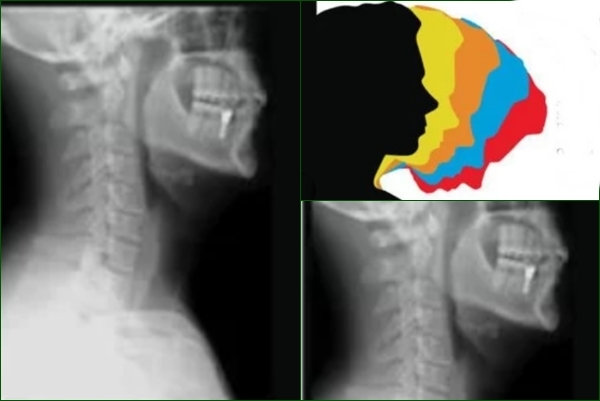

According to doctors at Amrita Hospital Faridabad, exposure to long hours in front of screens, coupled with poor posture and inadequate ergonomics in the workplace, is causing the young adults to be susceptible to spine-related conditions like “text-neck syndrome”.

The syndrome can be defined as where the neck muscles become strained and stiff, causing long-term spinal complexities, the experts said.

“Poor posture has become the most common cause of back and neck pain among our OPD patients. Remarkably, nearly 70 per cent of our OPD patients fall into this category. Poor screen etiquette is also a leading contributor to such pain. People often use their gadgets with their neck bent for prolonged periods, leading to a condition called “text-neck syndrome. Individuals between the ages of 25 and 45 are the most commonly affected by postural back pain,” said Dr Tarun Suri, Head of Spine Surgery at Amrita Hospital Faridabad.

Studies show that poor posture is the primary cause of neck and back pain in young and mid-age individuals, leading to work loss, hospital visits, and treatment expenses. Over time, it damages spinal discs, causes muscle spasms, and may lead to chronic pain, disc degeneration, and even surgery in severe cases.